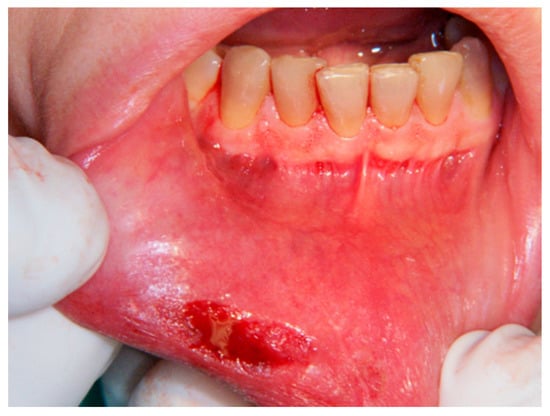

Aesthetic Treatment Outcomes of Capillary Hemangioma, Venous Lake, and Venous Malformation of the Lip Using Different Surgical Procedures and Laser Wavelengths (Nd:YAG, Er,Cr:YSGG, CO2, and Diode 980 nm)

1. Introduction